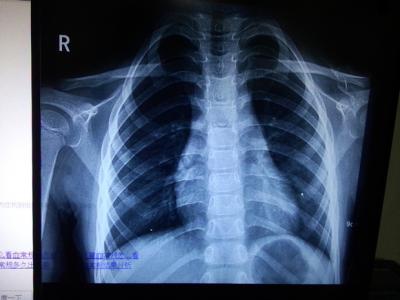

老公拍胸片影响备孕吗

当结婚之后大多夫妻都是把怀孕生宝宝放在首位的,现在为了生一个健康的宝宝,很多的夫妻都会选择去做一些检查,这是为了保证孩子的身体是足够的健康的。在这期间如果老公在拍X片,也是为了保证孩子的身体健康。那么老公拍胸片影响备孕吗?

只要不是传染性的疾病,拍胸片是不会影响备孕的,但是也不要频繁的拍X线,特别是备孕期女性,X光线对宝宝很有影响,首先,在怀孕前三个月是胎儿各个器官发育成型的时间,宝宝在这个时期对外界环境是非常敏感的,X线片非常安全和味甘,是不会影响胎儿畸形的,而且X线对宝宝没有什么太大的影响,所以,拍胸片根本不会导致胎儿畸形。

怀孕期间作为一个女性朋友一定要保证心情愉快,并且要做好孕期保健工作,注意要多休息,只有把身体调理到最佳状态,才能更好的备孕,尤其是对X片、胸片、CT等官方的检查是需要和老公一起做到一起的。健康的身体才不会影响到胎儿的正常发育。